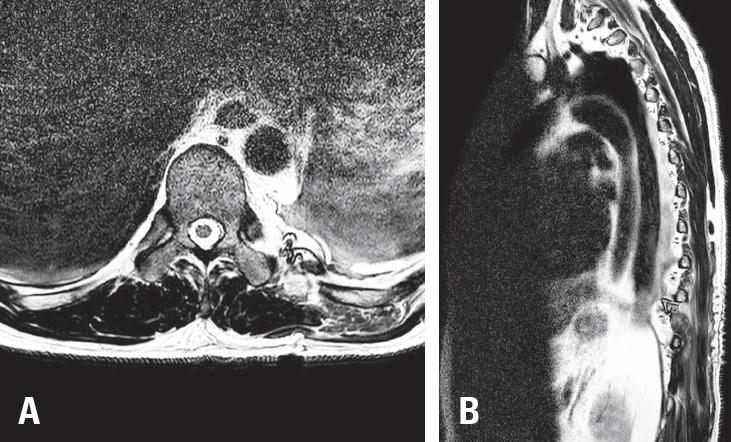

Postoperatively, the patient’s left flank pain resolved completely. He was discharged in good condition without complications. Follow-up MRI confirmed complete resection of the mass with no evidence of residual tumor (

Fig. 3A,

B).

Fig. 3.

Postoperative thoracic spine MRI. (A) Axial T2-weighted image showing complete resection of the previously identified mass.

(B) Sagittal T2-weighted image confirming no residual lesion.